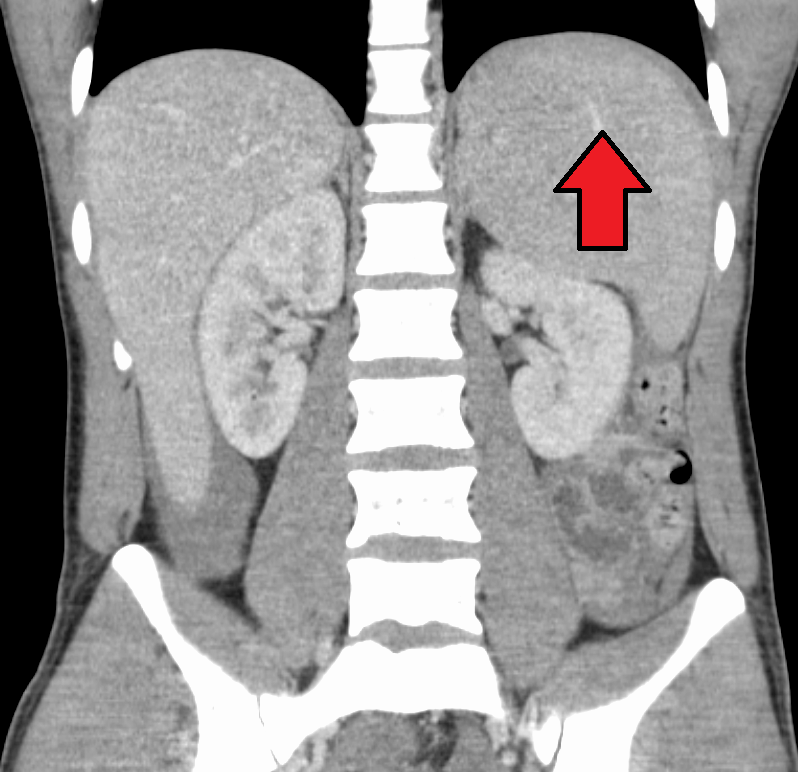

대부분의 감염성 단핵구증은 자연적으로 회복되지만, 드물게 합병증이 나타날 수 있다. 비장 파열, 용혈성 빈혈, 수막염, 뇌염, 횡단척수염, 길랭-바레 증후군 등이 발생할 수 있다.[26][63][64][43][65]비장 비대는 발병 2~3주차에 흔하게 나타나지만, 신체 검사로는 뚜렷하게 나타나지 않을 수 있다. 드물게 비장 파열이 발생할 수 있다.[26] 또한 약간의 간 비대증이 나타날 수 있으며,[23] 황달은 간혹 발생한다.[30][27]

비장 비대와 경부, 겨드랑이, 서혜 림프절의 림프절 종창은 감염성 단핵구증 진단을 의심하는 데 가장 유용하다. 반면에 경부 림프절 종창이 없고 피로가 나타나지 않는다면 감염성 단핵구증이 아니라고 생각할 수 있다. 비장 비대를 감지하는 신체 검사의 무감도는 감염성 단핵구증에 대한 증거로 사용해서는 안 된다는 것을 의미한다.[23] 신체 검사에서 구개의 점상 출혈이 나타날 수도 있다.[23]4. 2. 혈액 검사

비장 파열의 위험을 줄이기 위해 전문가들은 질병 발병 후 최소 3~4주 동안 또는 치료 의사가 결정한 비장 비대 소실 시점까지 접촉 스포츠 및 기타 격렬한 신체 활동, 특히 복부 압력 증가 또는 발살바 수기 (예: 조정 또는 역도)를 피하도록 권고한다.[23][52] 간비종이 심한 경우에는 복부에 충격을 받아 비장 파열이 일어난 사례도 있으므로 안정이 필요하다. 소아 등, 인두통이나 전신 권태감으로 인해 경구 섭취가 불량해진 경우에는 입원하여 수액을 투여할 필요가 있다.